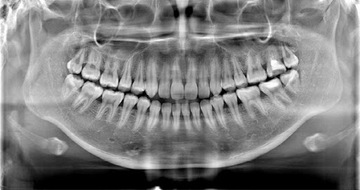

レントゲンは、大きないっぱい歯が映る分は

パノラマといいます。これはオルソパントモの略

小さいレントゲンはデンタルー歯科医院専用の

デンタルX線撮影といいます。

ぜひ、歯科医院に行かれた時に歯科医院スタッフの会話に耳をすまして見てください。